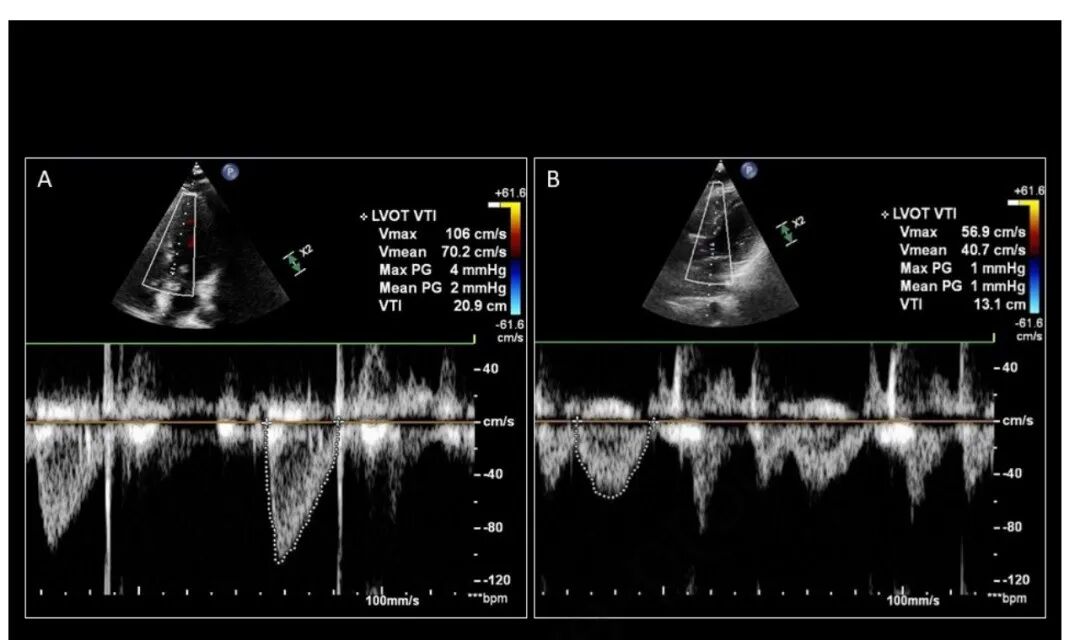

准确获取 LVOT VTI 跟踪非常重要。这要求 PW 多普勒采样线与 LVOT 内的血流平行。如果声波角度在 20° 以内,实际多普勒频移误差 ≤ 6%,导出的 SV 将是可靠的(图 4)。PW 采样点也需要放置在主动脉瓣近端,而不是 LV 腔本身内(图 5)。获得良好的 LVOT VTI 由内部“暗”和明亮“轮廓”的光谱包络表示。追踪 LVOT VTI 时,尽可能精确并尽可能接近外边缘非常重要(图 6)

图 4. 比较多普勒采样线 (A) 与血流平行与 (B) 离轴大于 20˚ 时产生的 LVOT VTI 差异。

图 5. 从 (A) LVOT 中适当的样本位置获得的 LVOT VTI 与在收缩末期捕获的主动脉瓣关闭,和 (B) 在 LV 腔中太近的位置之间的差异。